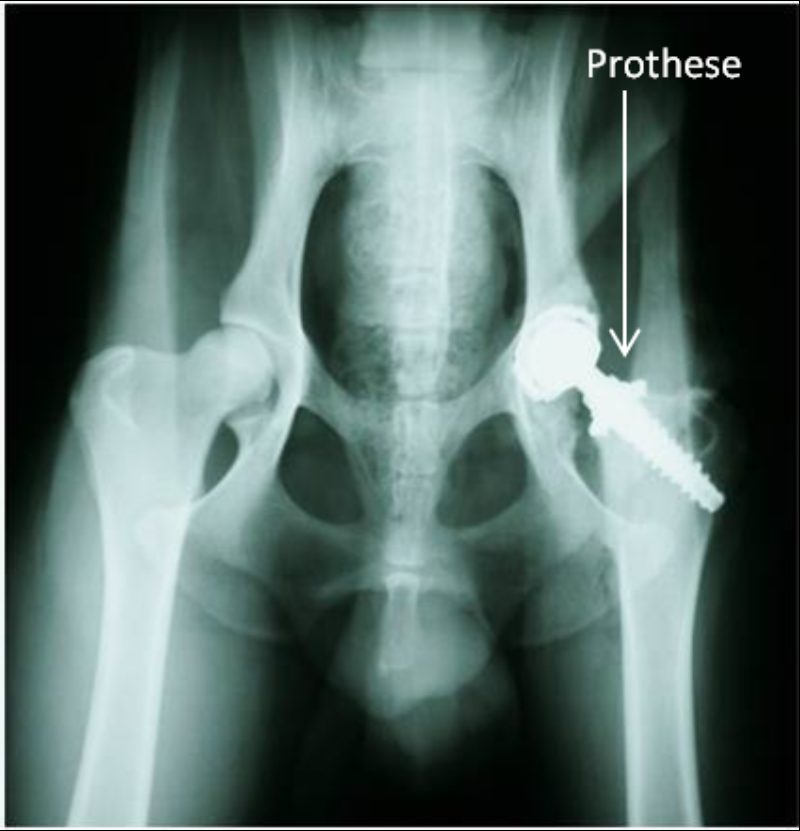

"Tyler", ein Dobermann-Mix, wurde am 18. August 2011 vom Nümbrechter Tierschutzverein "Menschen für Tiere e.V." in der Praxis vorgestellt mit dem Hinweis, er habe große Probleme mit seiner Hüfte und könne nur sehr schlecht laufen. Er war abgemagert bis auf die Knochen, lethargisch und litt sichtbar unter Schmerzen. Tyler zeigte einen deutlichen Muskelabbau und einen Hochstand des rechten Oberschenkels. Bei der Ganguntersuchung ist uns eine starke Lahmheit dieses Beines aufgefallen. Der Bewegungsumfang des Hüftgelenkes war deutlich eingeschränkt und bei der Streckung zeigte der Hund Schmerzen. Daraufhin haben wir eine Röntgenuntersuchung durchgeführt, wobei sich herausstellte, dass die Hüfte luxiert war, mit anderen Worten: der Oberschenkelkopf saß nicht in der richtigen Position. In einer funktionierenden Hüfte sitzt der Oberschenkelkopf in der Pfanne (s. Abb. 1). Bei Tyler saß der Oberschenkelkopf oberhalb der Pfanne. Er wies diese Veränderung seit langer Zeit auf, so dass der Oberschenkelkopf eine Pseudopfanne im Becken gebildet hatte (s. Abb. 2).

Aufgrund des Schweregrades der Verletzung war für Tyler die Wiederherstellung seines Hüftgelenks nicht mehr möglich. Die beste Option, Tyler ein schmerzfreies und voll belastbares Hüftgelenk zu ermöglichen, war daher ein künstlicher Hüftgelenkersatz.